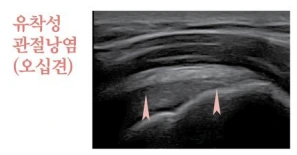

유착성관절낭염(오십견)

1.PNG

어깨질환 하면 가장 먼저 떠올리시는 대표적인 질환인 오십견의 정확한 병명은 ‘유착성 관절낭염’입니다. 관절막에 염증성 변화가 발생하면서 신축성이 감소하고 이로 인해서 어깨 관절의 통증과 운동 범위가 모두 감소하여 발병하게 됩니다. 보통 50대 이후에 갑자기 발병하는 경우가 많아 오십견이라는 이름이 있으나, 최근에는 스포츠 활동과 잘못된 자세 습관으로 인해서 오십견의 발병 연령이 점점 낮아지고 있답니다.

유착성관절염이 찾아오면 어깨 관절 부위에 강한 통증이 오고 움직이기도 어렵습니다. 이 통증은 점점 심해져서 방치하게 되면 수면장애까지 발생하게 됩니다. 또한, 어깨 통증이 손에까지 번지고 밤이 되면 통증이 악화되는 경향이 있습니다. 만약 당뇨가 있으시다면 더 오래 지속되는 경향이 있습니다. 보통 초반에 어깨 각도가 잘 나올 때는 욱신거리는 근육통처럼 나타나고 3주 정도면 좋은 결과를 얻을 수 있습니다. 그러나, 오래되어 어깨 각도 구축도 많이 되고, 진행하면 치료기간이 6주 이상 걸립니다. 초기에 진단 후 치료하시는 경우가 제일 결과가 좋은 질환입니다.